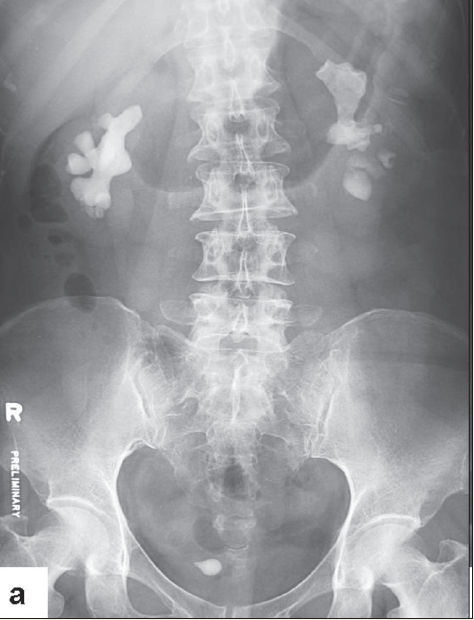

Laboratory testing. Urinalysis showed 5 to 10 white blood cells and 3 to 5 red blood cells per high-power field. Urine culture was negative. Plain radiography with a kidney-ureter-bladder (KUB) view revealed multiple opacities in the region of both kidneys and specifically in a location that corresponded to each renal pelvis. A subsequent intravenous urogram (IVU) confirmed the presence of bilateral renal staghorn calculi and a right ureteral stone within a ureterocele. A radioisotopic study showed the differential function of the right and left kidneys to be 44% and 56%, respectively, with scarring in the upper pole of the right kidney. Serum calcium, phosphate, urate, and blood urea (nitrogen, creatinine, and electrolyte levels) were normal.

Plain radiography of the abdomen with a KUB view reveals up to 70% of renal stones. Ultrasonography or unenhanced helical CT can detect more than 90% of renal stones.6,7 IVU was formerly the study of choice to confirm the presence of the stone, to provide an anatomical outline of the urinary tract, and to identify the presence and the degree of obstruction. CT is commonly available and is now considered the study of choice.

A supplementary IVU is indicated for renal pelvic stones, for caliceal stones larger than 1 cm, and after failure of extracorporeal shockwave lithotripsy (ESWL).

For patients with large renal stones, such as staghorn calculi, or with a poorly functioning kidney, radioisotopic renography should be performed to assess the differential renal function.